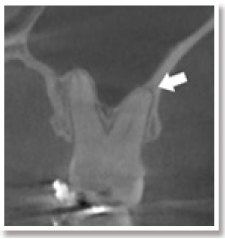

45歳女性、1年以上前から上の奥歯が咬むと痛く、大学病院でも治療を行ったが改善せず、当院の総合健診を受診されました。

その結果、根の中に病気があるだけでなく、歯根にひび(破折線)が入っていることがわかりました。

治療によって痛みは消失し、抜歯せずにすみましたが、違和感は残りました。

総合健診の結果、通常のエックス線写真だけ見つけにくい原因が見つかった一例です。

矢印の部分に黒く膿んでいる部分が見られます。

根の破折が疑われます。